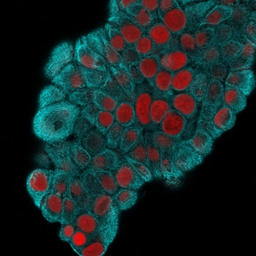

ICC/IF analysis of MeOH fixed MCF-7 Cells using GTX34651 Cytokeratin 19 antibody [KRT19/800].

Cyan : Primary antibody

Red : nucleus